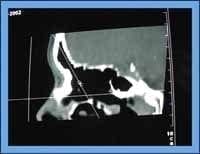

En la vista sagital de la reconstrucción multiplanar escenográfica se buscó en ostium del seno frontal tanto derecho como izquierdo, teniendo en cuenta la imagen de reloj de arena que forma el seno frontal, el ostium y el receso frontal (Figura 1) y se obtuvo el diámetro anteroposterior, para ello se tomo la distancia más estrecha entre la prominencia inferior de la pared anterior del seno frontal y la unión de la base del cráneo con la pared posterior del seno frontal.

Cintura ostium y parte inferior receso frontalFigura 1. Imagen de reloj de arena. Parte superior seno frontal, cintura ostium y parte inferior receso frontal.